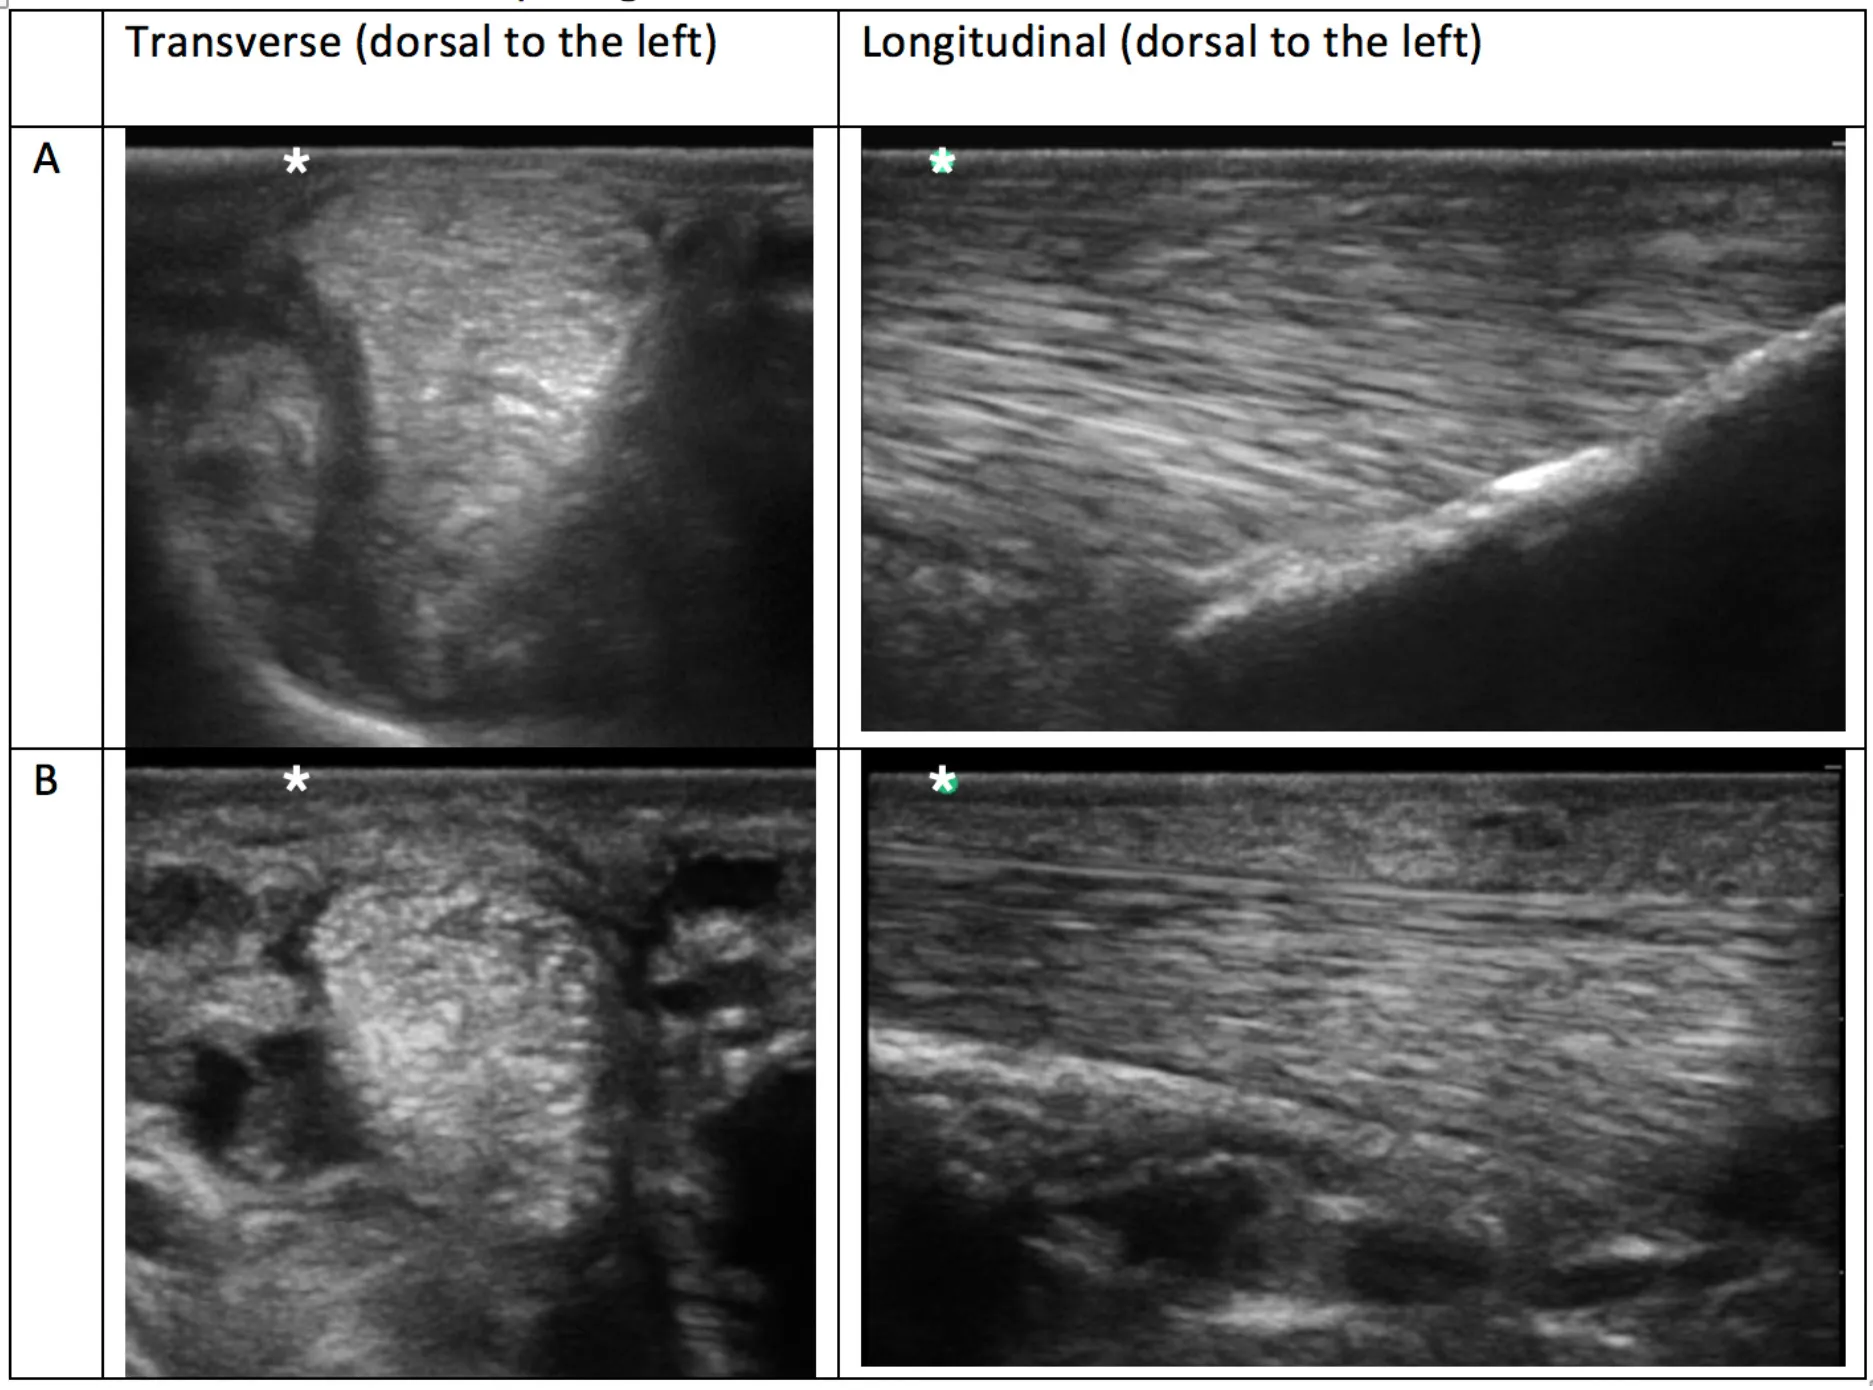

Combined data showing prevalence of each branch grade is represented in Figure 2, which demonstrates the frequency of grades for each individual observer, as well as where there was agreement. These grades are the overall branch scores, which have been assigned based on the worst grade given to an ultrasonogram slice in that branch. All but one horse had at least one branch that was grade 2. Grades given by observers A and B have been summarised and combined in Table 1: grade 0 0/960 (0%), grade 1 394/960 (41%) and, grade 2 554/960 (58%), and grade 3 12/960 (1%). Examples of each grade from horses in this study are shown in Table 2. The median number of grade 2 branches per horse for observer A was 4/8, and observer B was 5/8. The distribution in grades between forelimb vs. hindlimb SLBs was significantly different for both observers (observer A P = 0.001 and observer B P = 0.002). More grade 2 and 3 abnormalities were recorded in hindlimb SLBs. Combined data showed 255/480 (53%) of forelimbs and 321/480 (67%) of hindlimbs were graded 2 or 3. Comparison was also made for laterality in SLBs graded 2 or 3: 117/240 (48.7%) lateral and 131/240 (54.5%) medial for observer A, vs. 148/240 (61.1%) lateral, and 170/240 (70.8%) medial for observer B. The prevalence of grade 2 or 3 SLBs was higher in medial branches for both observers, but was only statistically significant for observer B (P = 0.026), not for observer A (P > 0.05).

Table 2. Example ultrasonograms in transverse and longitudinal for grade 0–3 branches taken of SLBs from horses included in this study.

Table 4. Comparison ultrasonograms taken from a population of elite level showjumping Warmbloods having no recent history or clinical signs of suspensory ligament branch (SLB) injury.